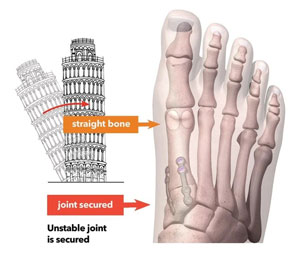

A common misconception is that a bunion is simply a "bump" that can be "shaved off." But, bunions are more than a bump – they are complex 3D problems caused by an unstable joint in the middle of the foot. While the majority of bunion surgery is only 2D and fails to address the root cause, Lapiplasty® provides a 3D correction and secures the unstable joint.

While traditional 2D osteotomy surgery merely cuts & shifts the bone to address the cosmetic bump, Lapiplasty® 3D Bunion Correction™ does more — it corrects the entire bone in 3D and secures the unstable foundation to get you back on your feet quickly in a walking boot. The Lapiplasty® Procedure has also shown low recurrence; 97% and 99% maintain 3D correction in 13 and 17 months respectively.

- Returns entire bone to normal alignment; a 3D correction

- Secures the root cause; an unstable joint